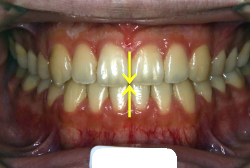

歯科矯正用アンカースクリューを用いた症例(骨格性反対咬合 非抜歯治療)

「ものがうまく噛めない」という主訴で来院したケースです。診断の結果、「骨格性反対咬合に伴う咬合不良+軽度叢生」と判明しました。原因としては特に下顎の左側が過成長したため、骨格性反対咬合になり、特に左側での噛み合わせが非常に悪くなっていると診断しました。初診時の写真を見ると、上下の正中線の大きなズレ、左側の噛み合わせの不良がはっきり分かります(黄色の矢印と緑の矢印は一致しているのが正しい状態です)。